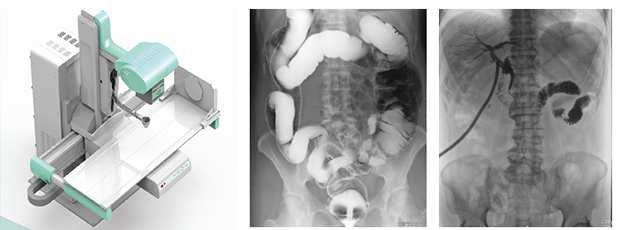

在動(dòng)態(tài)dr成為普放領(lǐng)域大趨勢(shì)的當(dāng)下,越來越多的醫(yī)療器械企業(yè)宣稱自家擁有動(dòng)態(tài)dr產(chǎn)品。據(jù)了解,目前真正掌握核心動(dòng)態(tài)探測(cè)器技術(shù)的企業(yè)寥寥無幾。被蒙蔽的消費(fèi)者根本區(qū)分不清楚真正動(dòng)態(tài)dr是什么樣的,這里,小編就來科普一下真正動(dòng)態(tài)dr必須具備的要素?

1、真正動(dòng)態(tài)dr需全面符合我國(guó)新監(jiān)測(cè)標(biāo)準(zhǔn)。通過智能算法軟件進(jìn)行對(duì)拍攝時(shí)的輻射劑量進(jìn)行監(jiān)控并且會(huì)在超劑量標(biāo)準(zhǔn)值時(shí)進(jìn)行報(bào)警以及采取強(qiáng)制關(guān)閉設(shè)備措施,全面呵護(hù)患者健康。

2、真正動(dòng)態(tài)dr要采用高亮度碘化銫非晶硅動(dòng)態(tài)平板探測(cè)器,能實(shí)現(xiàn)毫秒級(jí)的動(dòng)靜切換,將動(dòng)態(tài)透視造影與靜態(tài)拍片完美結(jié)合,這個(gè)切換速度保持在0.7秒左右才能滿足臨床要求。

3、真正動(dòng)態(tài)dr是能夠?qū)崿F(xiàn)高幀率動(dòng)態(tài)視頻拍攝的設(shè)備,因此能達(dá)到≥30/S,達(dá)到日本島津同樣水平的動(dòng)態(tài)dr才是真正有價(jià)值的動(dòng)態(tài)dr。這也是與其他偽動(dòng)態(tài)dr較大的區(qū)別。

4、真正動(dòng)態(tài)dr需要具有iDGC智能低劑量濾線柵控制功能,與傳統(tǒng)手動(dòng)人工插拔濾線柵不同的是,本功能能夠根據(jù)患者的人群年齡、所需臨床拍攝部位等條件可進(jìn)行智慧化自動(dòng)切換合適的濾線柵來獲取高質(zhì)量圖像,以保證不同患者受到低限度的輻射劑量。

5、真正動(dòng)態(tài)dr需要標(biāo)配智能脈沖曝光技術(shù),優(yōu)質(zhì)的圖像需要高穩(wěn)定,高頻率的動(dòng)態(tài)高壓發(fā)生器與動(dòng)態(tài)平板探測(cè)器進(jìn)行協(xié)同,使用傳統(tǒng)的連續(xù)曝光輻射劑量大,圖像清晰度也較差,而采用脈沖曝光技術(shù)可以降低50%以上患者所受輻射劑量,同時(shí)減少運(yùn)動(dòng)偽影導(dǎo)致的圖像模糊,提高成像清晰度,輔助醫(yī)生進(jìn)行更加準(zhǔn)確的診療。

6、真正動(dòng)態(tài)dr需要具備iACF智能高清點(diǎn)片自動(dòng)裁切和智能圖像緩存調(diào)用系統(tǒng)等圖像算法功能,較大程度提高操作體驗(yàn)感,支持醫(yī)生回放造影視頻,輔助診斷。

動(dòng)態(tài)dr大大提高了普通放射設(shè)備準(zhǔn)確診斷的能力,為臨床創(chuàng)造了價(jià)值。好了,有關(guān)真正動(dòng)態(tài)dr就介紹到這了,如果你想了解更多,歡迎關(guān)注“普朗醫(yī)療器械網(wǎng)”,我們會(huì)定期的更新一些新的內(nèi)容供大家瀏覽閱讀。